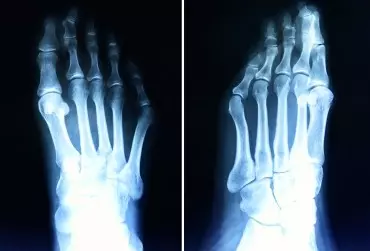

Hallux valgus – postępowanie fizjoterapeutyczne

Haluks (hallux valgus) to koślawe zniekształcenie palucha w stawie I śródstopno-paliczkowym (metatarsophalangeal – MTP). Polega na koślawym ustawieniu palucha i szpotawym ustawieniu I kości śródstopia. Kąt pomiędzy osią palucha a osią I kości śródstopia przekracza 20°. Skutkiem tego jest uwydatnienie po stronie przyśrodkowej stopy głowy I kości śródstopia.